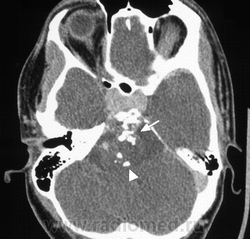

ID: 4555 Chordoma Dr Frank Gaillard - 12 Sep 2008 MRI and CT demonstrate a large destructive soft tissue mass arising from...

ID: 7880 Chordoma Dr Frank Gaillard - 20 Dec 2009 This lesion was resected and confirmed to be a chordoma.

ID: 5269 Chordoma - mainly anterior growth Dr Frank Gaillard - 29 Dec 2008 MRI through the base of skull demonstrates a large midline mass centred ...